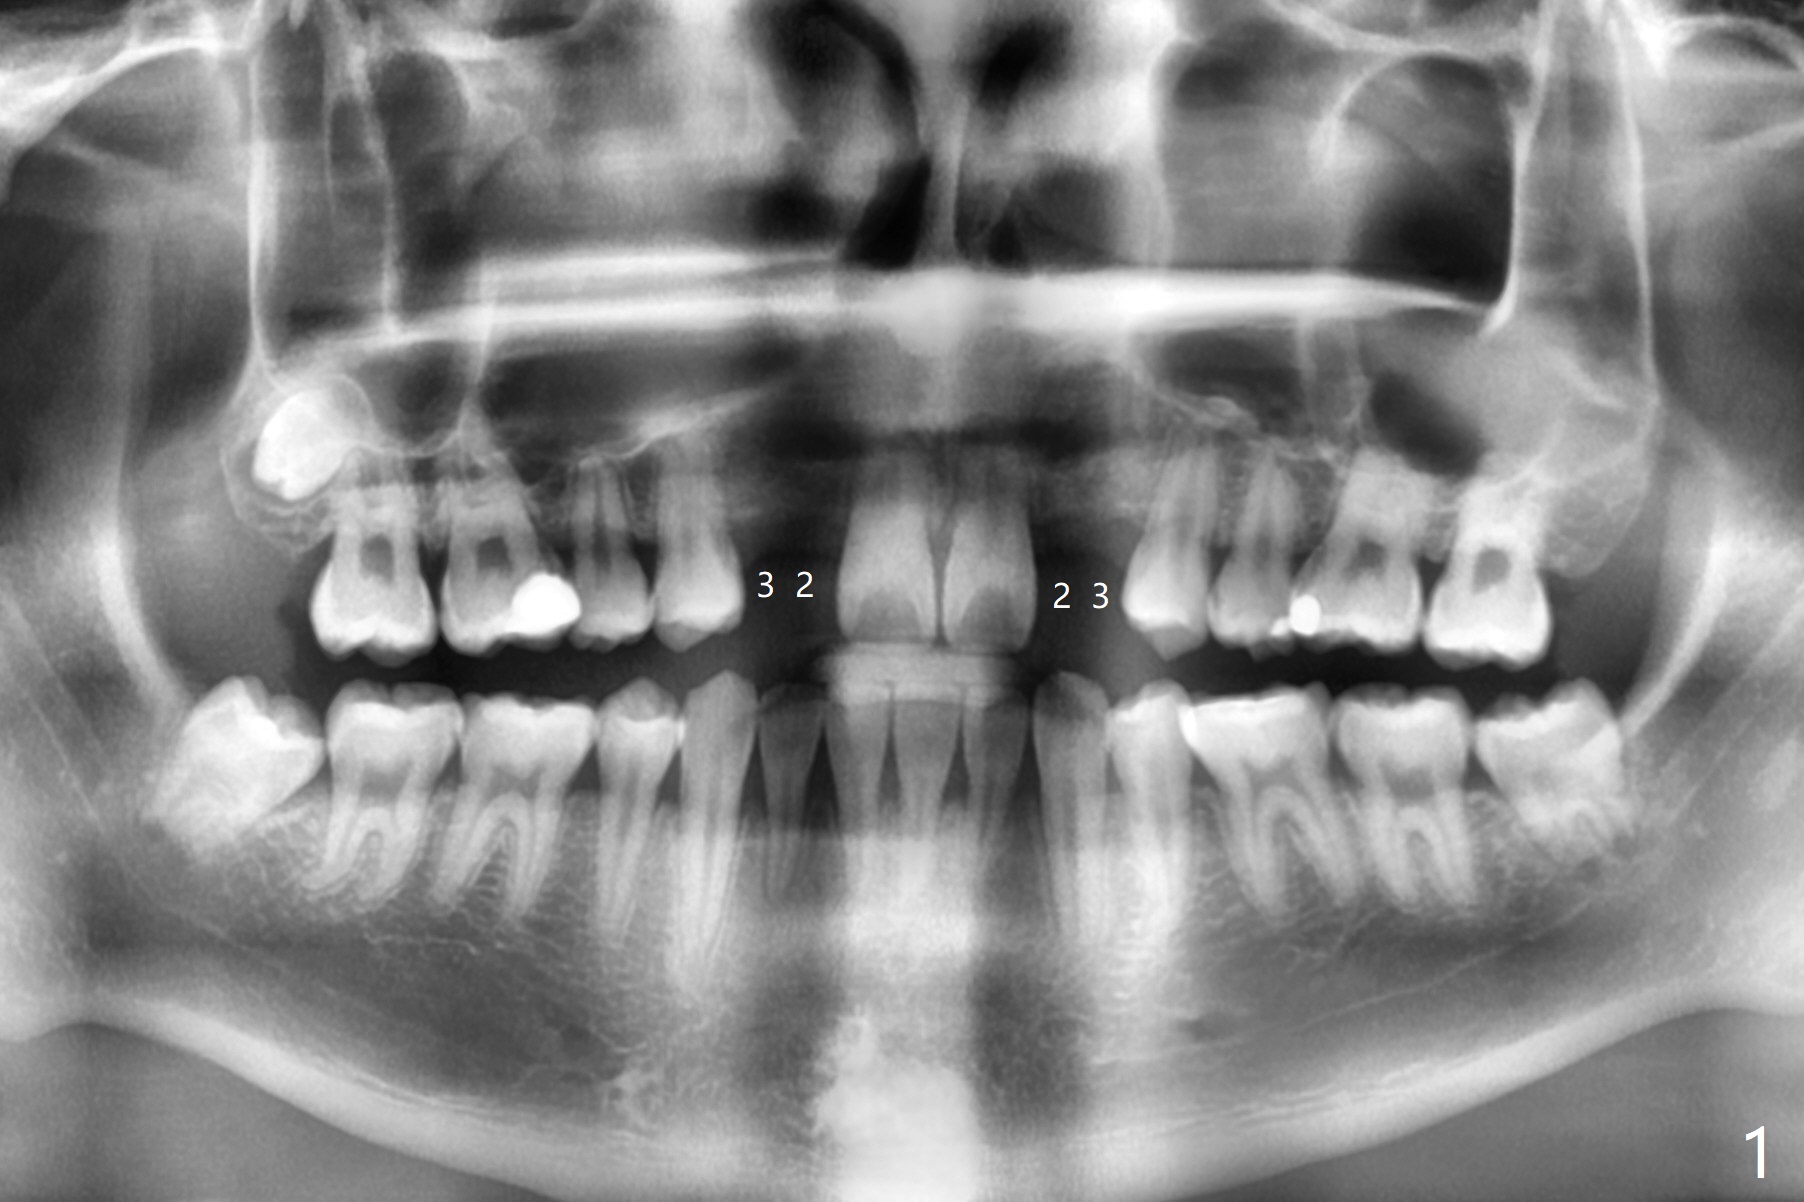

18岁男先天缺失上颌2,3(图一:双侧),2严重颊侧骨壁凹陷(图二,三:2),准备在两侧3种植(图二,三:绿色),做悬臂桥,右上植体3.5乘10毫米,但是必须用带有角度基台修复。而左上3用同样大小植体,颊侧螺纹暴露(图三 B),你会怎么处理?一个月病人到外州上学,而且治疗必须在十九岁前完成,保险可多付钱。为了能在颊侧植骨(图四红圆圈),在左上1近中做一个垂直切口(图五,六红实线),潜行分离骨膜直到4近中(红虚线),并且放置骨块,让骨膜离开颊侧骨板,钻洞时不损伤骨膜。植体放入后,检查颊侧骨块是否足够,最后放置PRF膜,缝合。